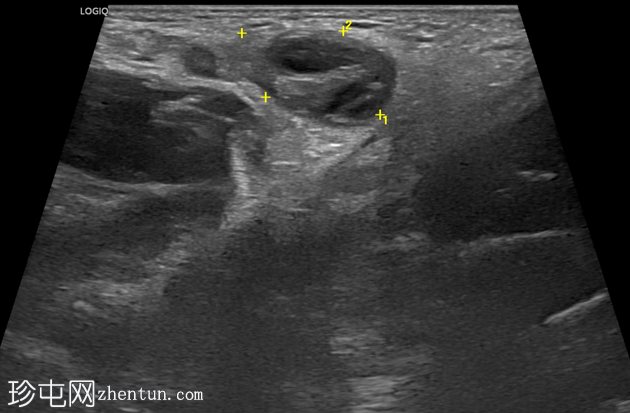

右侧努克氏疝管长约6毫米,内含部分子宫和卵巢(大小约1.5 x 1厘米)。在整个检查过程中,这些组织均保持原位。

上述超声特征清晰地显示了努克氏疝管的内容物及其延伸范围;其中包含患者的一侧卵巢和部分子宫组织。

这些特征符合卵巢努克氏疝的诊断。